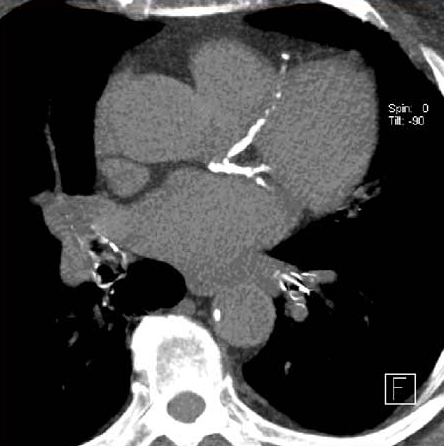

En las personas que se sometieron a una TC de tórax de baja dosis para la detección del cáncer de pulmón, la presencia de calcio en la arteria coronaria fue un predictor independiente de muerte por cualquier causa y eventos cardiovasculares, incluso después del ajuste por muerte no cardiovascular. Canadian Medical Association Journal, 2 de diciembre de 2024.